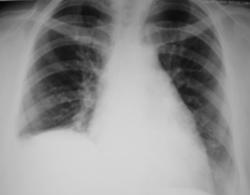

Неделю тому, пациентка выписана из терапевтического отделения, где находилась на стационарном лечении, по поводу пневмонии. Сегодня пациентка направлена на рентгенологическое исследование ОГК с диагнозом "Пневмония". Произведена рентгенография в стандартных проекциях - прямая и правая боковая, которая дополнена томографией в боковой проекции.

По совокупности признаков ИМХО справа вытекает обструктивный процесс в с/долевом и нижнезональном бронхах, Br6 не поражён (жаль сами бронхи почти не видны[те же 640х480пикселей]). Это сочетается с плевральным экссудатом м/долевым и диафрагмальным.

Сегментарные ателектазы нижней зоны правого легкого, подьём правого купола диафрагмы, плевральный выпот. Для начала выполнил бы УЗИ и спунктировал плевральную жидкость. После анализа характера жидкости-определился с дальнейшим ведением. Если есть сомнения-сделал бы КТ.

Похоже, я опять не в ногу.... Согласен с базальным гидротораксом справа, возможно в стадии осумкования (надо на латероскопе посмотреть). А вот с ателектазами нижней доли правого легкого не согласен: корень не смещен.

Оказывается во время операции был пересечен нерв. Вот рентгенограммы - 1 сделана после операции, вторая - через 1 месяц.

Ну уж коли за 10 мес. динамики нет, значит всё дело в релаксации диафрагмы, а выпота мало и обтурции бронхов, видимо, нет. Поджаты и уже не расправятся S4, S5, S7, S8, S9, S10.